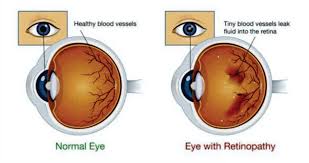

Do you offer laser vision correction?Yes, we provide consultations for LASIK and other laser vision correction procedures. Our experts work closely with trusted surgeons to ensure safe and precise outcomes.What options are available for treating dry eyes?We offer customized treatments, including lubricating drops, prescription medicines, and advanced solutions such as punctal plugs or light therapy for long-term relief.Can I get my glasses on the same day?In most cases, yes. Our in-house optical center can prepare your prescription glasses on the same day or within 24 hours, depending on lens type and availability.Do you provide treatment for glaucoma and cataracts?Yes, we specialize in diagnosing and managing glaucoma, cataracts, and other eye diseases. Our team ensures timely treatment plans and advanced surgical options when needed.Are contact lenses suitable for children and teenagers?Absolutely. With proper guidance and care, contact lenses can be safely worn by children aged 10 and above. Our specialists help select lenses best suited for young eyes.